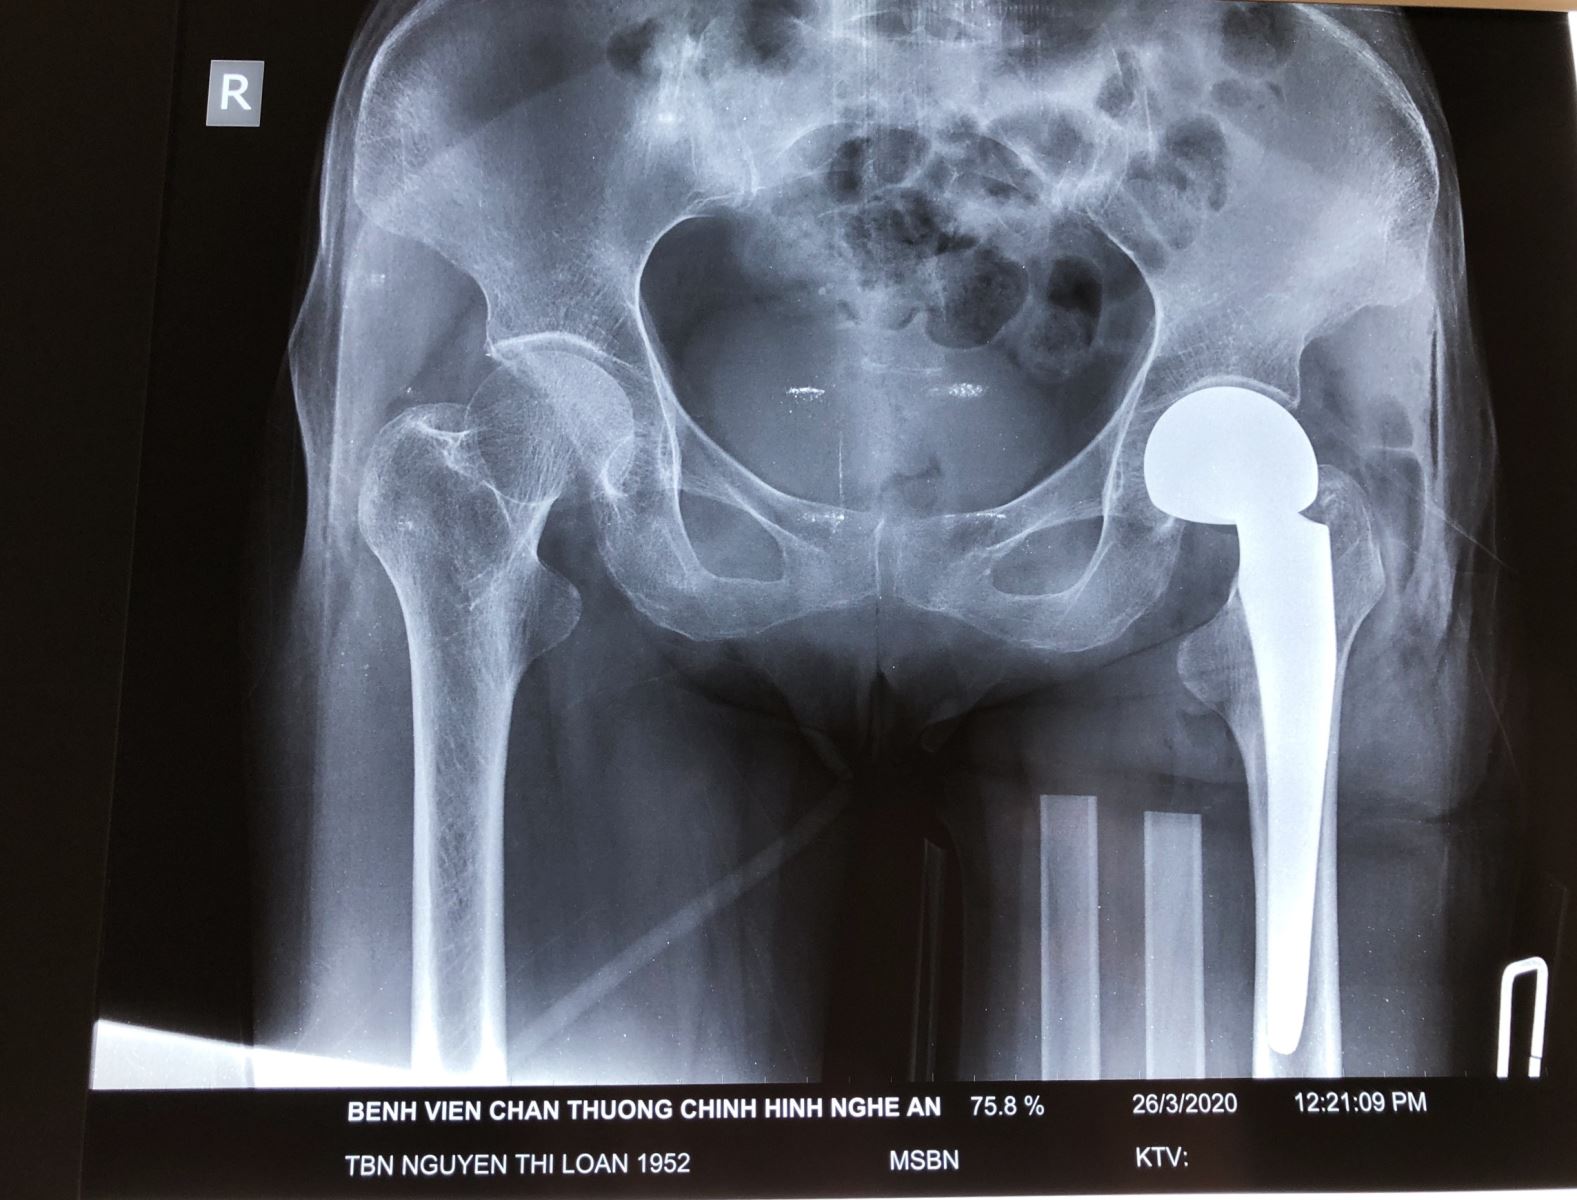

Sau khi tiến hành hội chẩn, bệnh nhân được chỉ định phẫu thuật thay khớp háng bán phần. Ca phẫu thuật được tiến hành thành công bởi kíp mổ của ThS, Bác sĩ Nguyễn Hoài Nam – Giám đốc Bệnh viện và các cộng sự.

Sau mổ bệnh nhân diễn biến ổn định. Tuy nhiên do bệnh lý nền Parkinson nên việc phục hồi chức năng sau mổ của bệnh nhân gặp nhiều khó khăn. Nhưng được sự chăm sóc, hướng dẫn nhiệt tình của đội ngũ y bác sĩ giàu kinh nghiệm, chỉ 7 ngày sau mổ, bệnh nhân đã tập đi lại được với dụng cụ hỗ trợ.

Hình ảnh phim chụp Xquang của bệnh nhân trước và sau phẫu thuật thay khớp háng